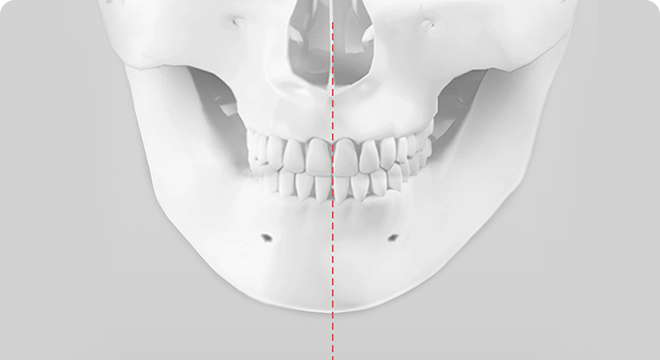

ㅅ절골술은 턱끝의 길이를 조절하여 길게 하거나 짧게 줄일 수 있으며, 무턱이나 주걱턱을 보형물이나 뼈 이식 없이 효과적으로 개선할 수 있습니다. 또한 동시에 비대칭이 심하거나 넓은 턱끝도 부드러운 V라인 턱끝을 만들 수 있으며, 턱끝 신경과 치아뿌리를 피해 절골하기 때문에 신경과 치아 손상없이 안전하게 수술할 수 있습니다.

턱끝의 위치나 모양이 비대칭일 경우 ㅅ절골술을 통해 비대칭을 70~90%까지 교정할 수 있습니다.